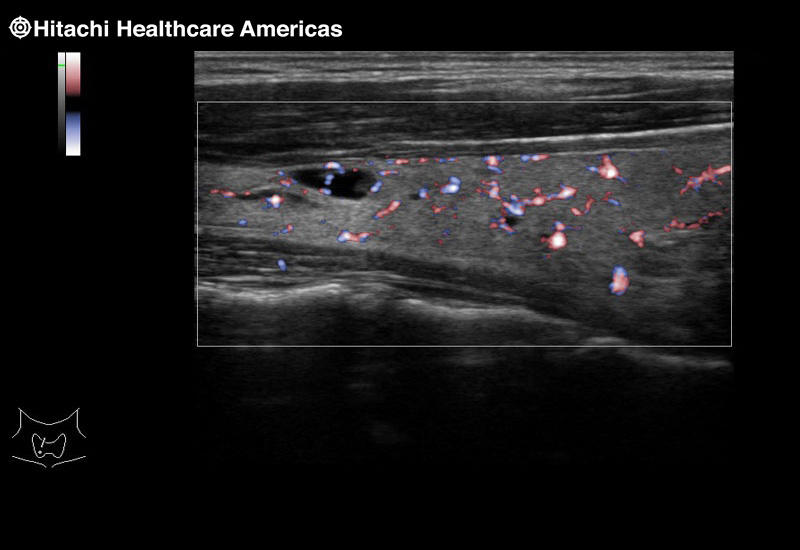

Superior guidance for all applications

Fujifilm Healthcare Americas is committed to designing tools that help surgeons navigate inside the human body and provide the necessary information to immediately make critical surgical decisions.

Fujifilm Healthcare's dedication to Surgeons provides outstanding ultrasound technology, professional support and the specialized tools necessary to best perform comprehensive real-time ultrasound imaging in Breast Surgery, General Surgery, Laparoscopic Surgery, Neurosurgery, Robotic Surgery and Surgical Oncology.

The Arietta 65 has many advanced and unique probes that fully cover the expanding range of procedures that benefit from ultrasound guidance.

The Arietta 65 has many advanced and unique probes that fully cover the expanding range of procedures that benefit from ultrasound guidance.